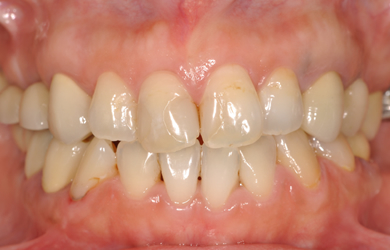

治療後

• 治療後